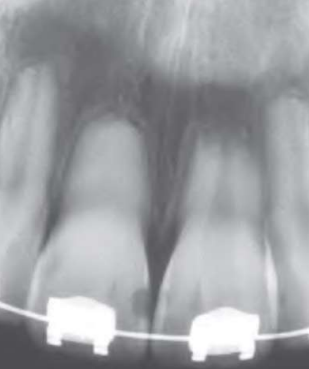

Periapical(radicular) cysts | Rest of Malassez 被刺激 | - | - | true/ periapical cyst 圓形的光通性包圍根尖 |

牙根吸收, 2cm ↑ 根管治療無效 ![]() |